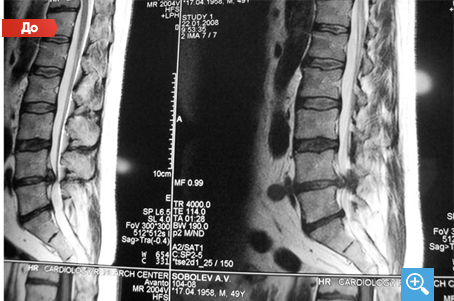

Секвестрированная грыжа

После 6 месяцев Детензор-терапии по одному сеансу 1 раз в день по 45 минут отмечается очевидный регресс секвестрированной грыжи межпозвонкового диска с 6,7 мм до 2,8 мм